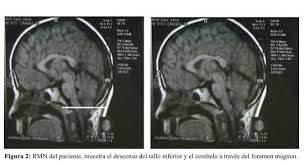

Tipo II. Es el desplazamiento hacia el raquis cervical,de, además de las amígdalas, del vermis cerebeloso, IV ventrículo y bulbo raquídeo, de una forma total o parcial. Este tipo específico de malformación se llama también de "Arnold-Chiari".

Tipo III. Consiste en el desplazamiento del cerebelo y tronco cerebral al interior de un meningocele cervical.

El diagnóstico es radiológico y el método de elección es la Resonancia Nuclear Magnética.